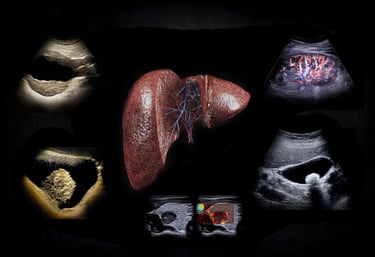

Hands-On Abdominal Ultrasound Imaging & Doppler

A Three Day Guided Experience

Learn to acquire, analyze, and trust abdominal ultrasound findings through live scanning, direct faculty guidance, and structured repetition—exactly as ultrasound is used at the bedside.

The abdomen is a complex landscape of organs, spaces, and fluid dynamics—and static images rarely tell the full story. This course matters because it teaches you to move beyond snapshots and into pattern recognition informed by respiration, peristalsis, and physiologic context.